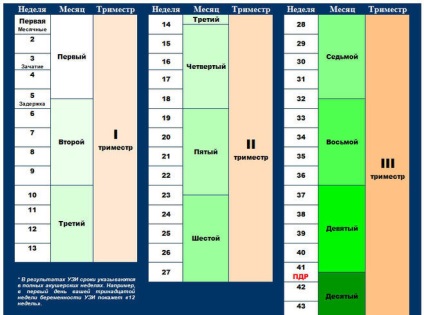

Hagyományosan, a kifejezés minden terhesség hozott kiszámításához az első kilenc hónapban, de a 37 terhességi hét - ez a kezdete a tizedik hónap. Az a tény, hogy az ideális időszak a vemhesség 280 nap -, hogy ebben az időszakban a baba ideje, hogy teljesen érett és fejlesztése a szülés. Egy szülészeti hónap áll 28 nap, azaz 4 hét.

Következésképpen 280 nap - 10 hónap nőgyógyászati által működtetett szülésznők, ha számít ideje a szülés. A hétköznapi emberek alig több mint 9 naptári hónap. 37 héttel a baba is kérni kell szabadítani az adott napon, akkor a legintenzívebb, és a régóta várt idő.